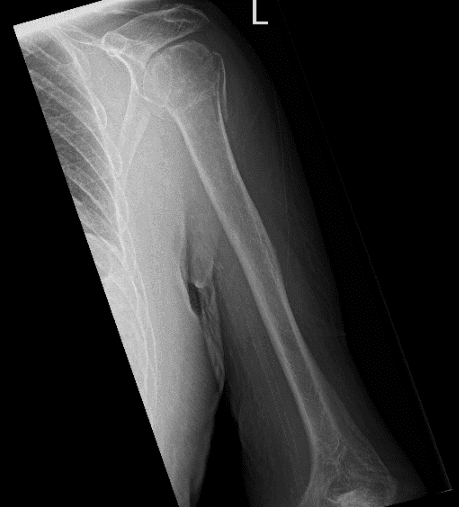

Paciente visto hoy con quejas con su debería ser la izquierdar. Él afirmó que se cayó de una escalera. Y su hombro izquierdo es el más afectado. Lleva su radiografía consigo. La radiografía detectó una fractura conminuta de la cabeza y el cuello humerales, y no hubo cambio en la posición de los fragmentos de fractura en comparación con el hombro izquierdo.

Radiografía del hombro izquierdo

El resultado de la tomografía computarizada también se discutió al paciente: la fractura proximal conminuta del húmero está impactada y el componente de fractura ligeramente angulada en el cuello quirúrgico, fragmento de fractura ligeramente desplazado en la mayor tuberosidad y una fractura sutil no desplazada en la menor tuberosidad.

Los huesos son osteopéticos. No hay evidencia de puentes óseos. Existe un derrame articular glenohumeral.